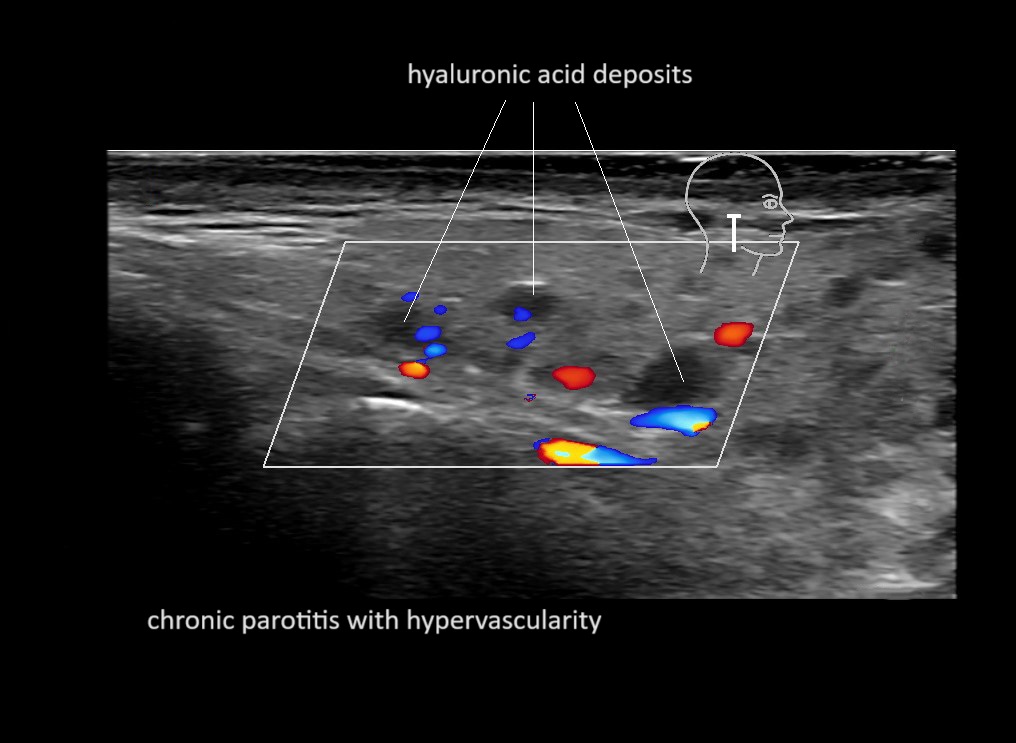

With ultrasound signs of inflammation can be visualized. Edema can be seen as a hyperechoic appearance of the subcutaneous fat, sometimes separated by hypoechoic fluid filled area’s, known as cobblestone appearance. Increased vascularization (hypervascularity) can be seen on colour Doppler. An abscess will appear as a fluid collection appearing as an irregular hypoechoic area with heterogeneous internal echoes and a thickened wall. Posterior acoustic enhancement can be present, and there is vascularity around but not within the mass. Under ultrasound guidance, abscesses can be managed by needle aspirations (18G) under antibiotic cover.